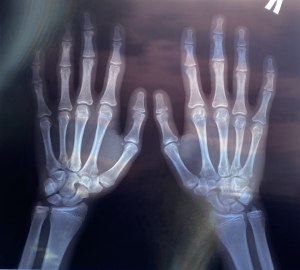

1. Возможно, ты достигла своего окончательного роста в 11 лет, но это не исключает возможности роста в будущем.

3. У девочек обычно происходит период активного роста в возрасте от 10 до 14 лет, но некоторые могут продолжать расти до 18-ти лет.